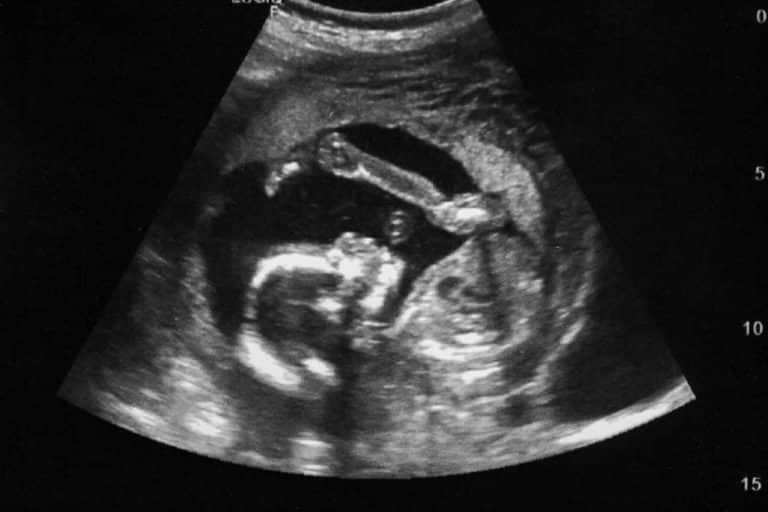

An ultrasound is simply a method of creating an image with the use of high frequency sound waves, so high they cannot be heard by human ears. The sound waves bounce back to the equipment to form the image on a monitor. The procedure is totally safe and painless for both you and your baby.

The ultrasound is given after the pregnancy is confirmed and your pregnancy has advanced. If the ultrasound is given too early in the pregnancy, the image of the baby will not be defined.